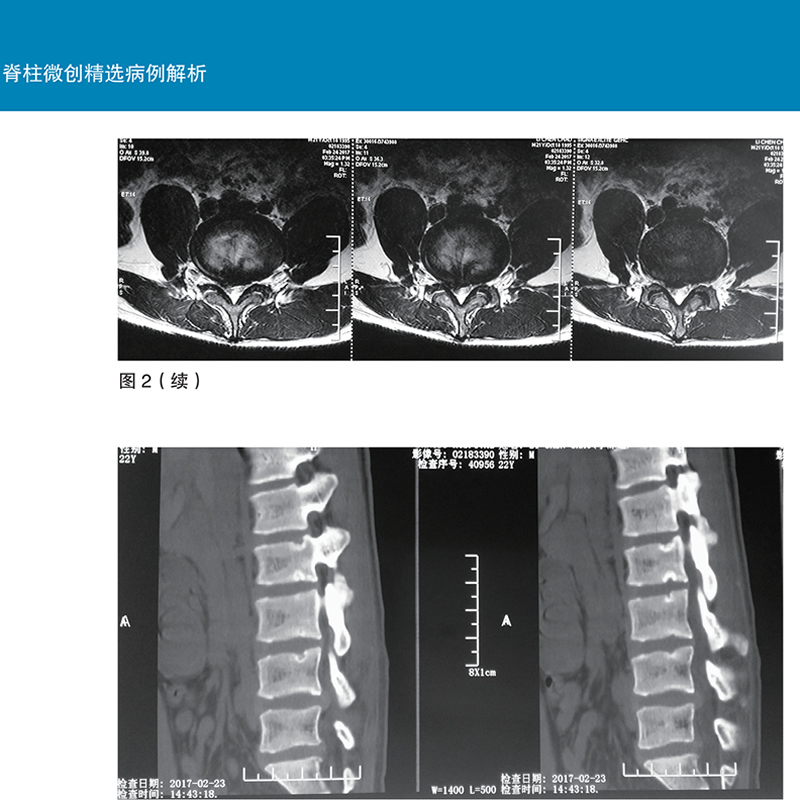

正版包邮 脊柱微创精选病例解析(附手术视频) 钱济先 脊柱介入造影激光修复神经根阻滞内镜手术方案 脊柱外科医学书 世界图书出版